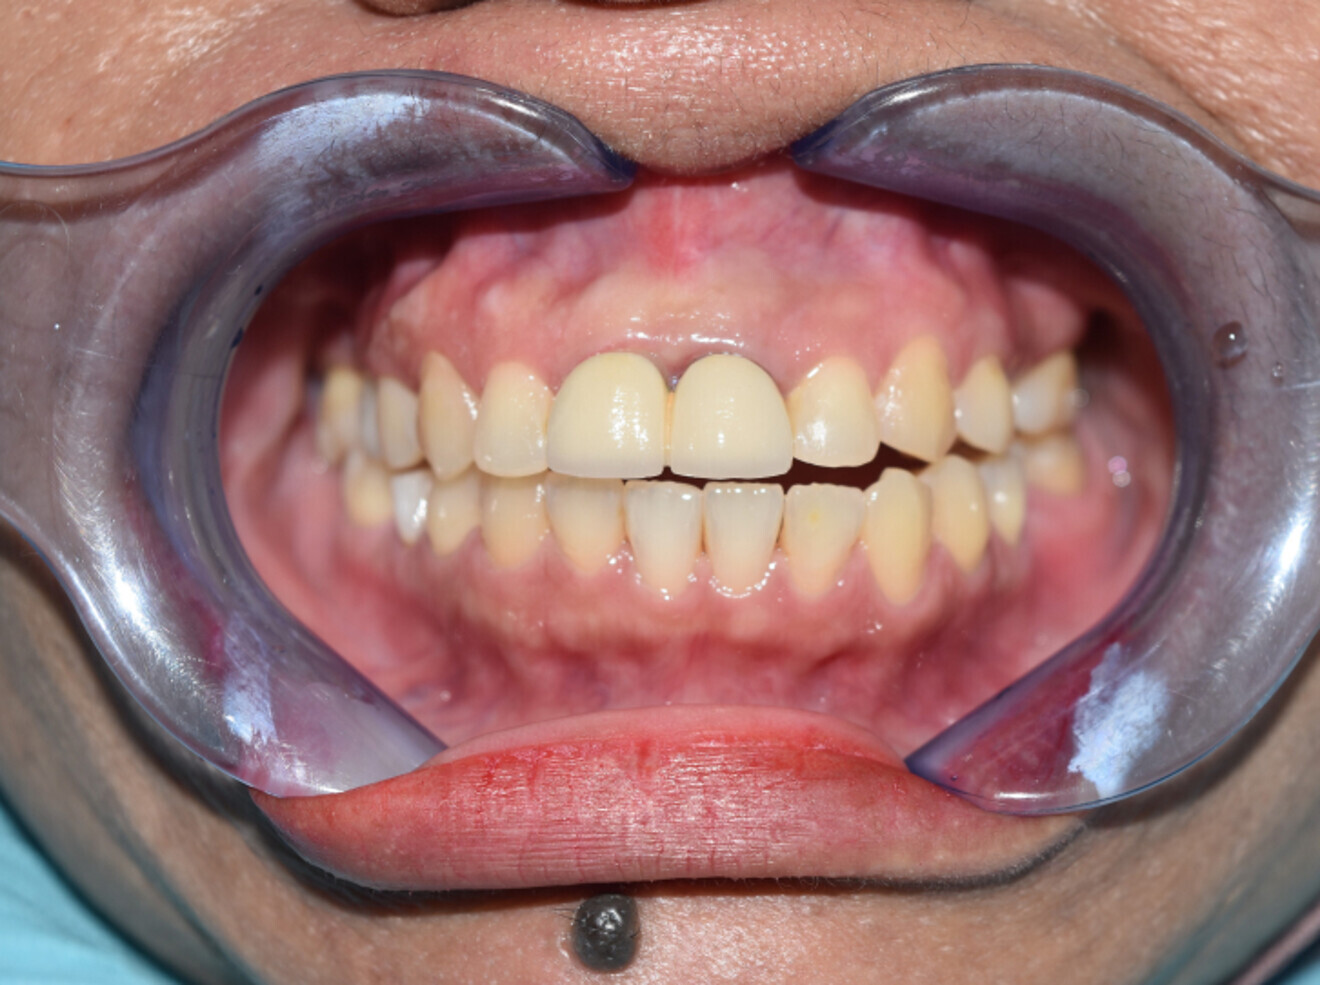

Fig. 14a: After debond.

Fig. 14b: 2 years later.

Fig. 14c: 4 years later.

Fig. 14d: 6 years  later.

In both cases, 2-unit bridge was prepared immediately after debonding of brackets with Hawley retainer as retention while temporary bridge is in place. After final porcelain fused metal bridge is cemented, Hawley retainer was replaced by essix retainer. Both patients found Hawley retainer intolerable and reminded them of dentures and requested for Essix instead. Additionally, in both cases their essix retainer is no longer worn due to loss of interest by the end of first year post orthodontic treatment.

In case 1, further failure of other remaining teeth occurred over the years due to poor oral hygiene and care. Nevertheless, contact points between upper anteriors from canine to canine remain intact with minimal change to occlusion. However, in case 2, although anteriorly the contact points too remained intact, anterior open bite developed over the years.

Both cases shared a similar success in terms of increased longevity of upper central incisors in general. Both were experiencing occlusal trauma prior orthodontic treatment with mobility. Splinting of the central incisors with the 2-unit bridge helped in reducing the load of occlusal trauma. Retention of median diastema closure proved to be successful up till maxillary canines post orthodontic treatment despite of removable retainers’ absence.